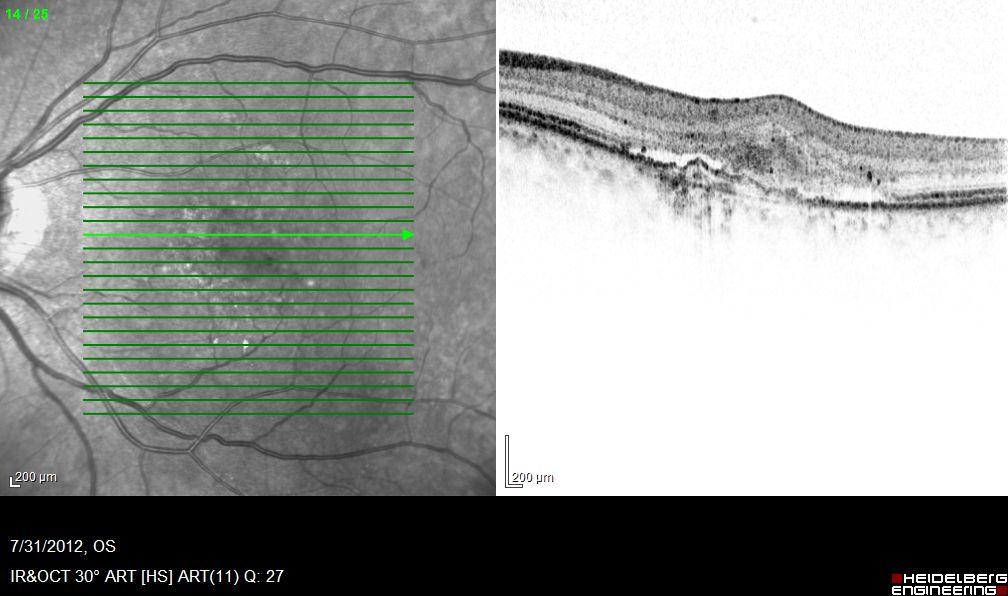

醫生透過散瞳眼底檢查及「光學相干斷層掃描」,診斷黃斑區水腫、出血或萎縮情況,來掌握病情變化。